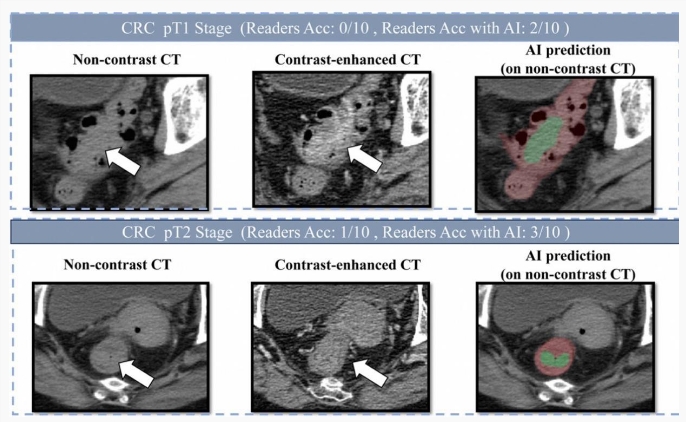

阿里巴巴发布创新癌症AI模型 助力肠癌筛